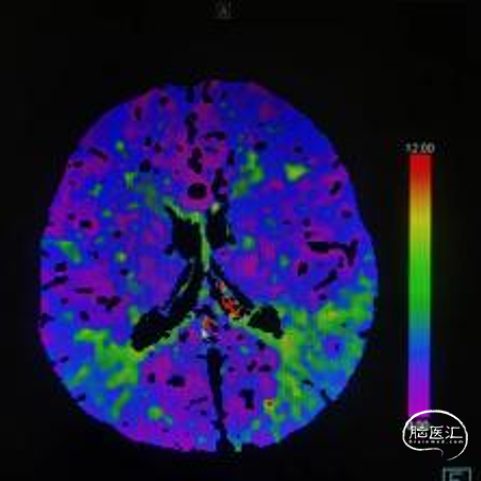

➢术前CTP

MTT